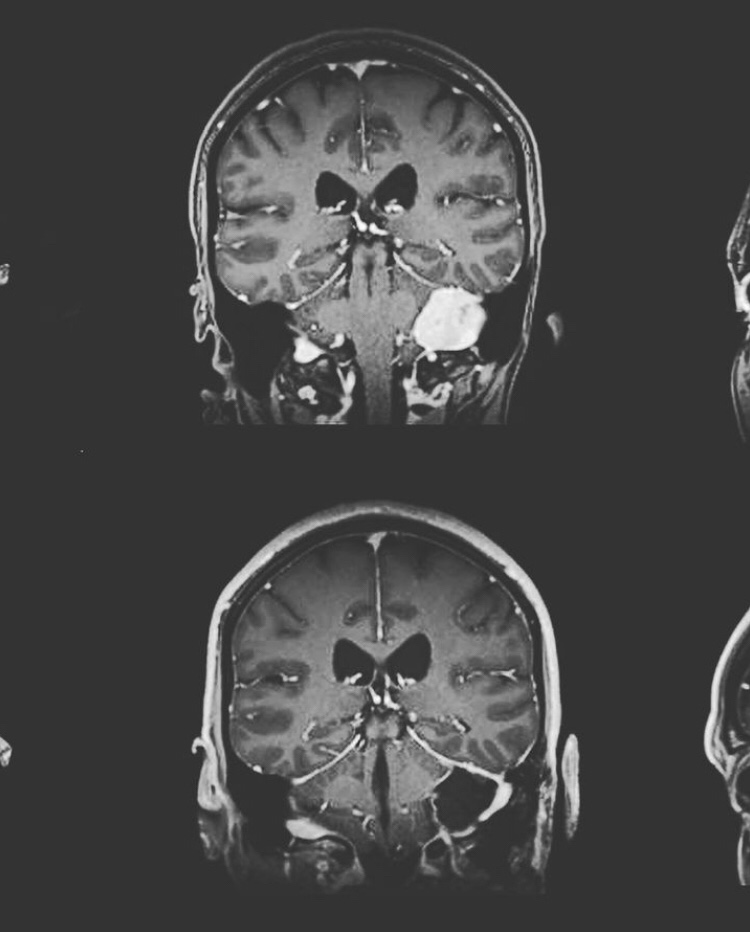

Hace unos meses haciendo un chequeo anual de mi cuerpo, me consiguieron a través de una resonancia magnética un visitante benigno en mi cabeza, que por su tamaño demostraba que llevaba mínimo una década creciendo cómodamente.

Esto quería decir que iba a seguir creciendo y quizás en unos años podía comprometer mi salud y mis funciones.

La única opción que tenía era sacárlo a través de una craneotomía.